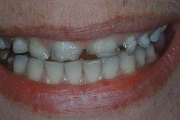

Laste ja noorukite söömishäired. Anorexia nervosa, Bulimia nervosa